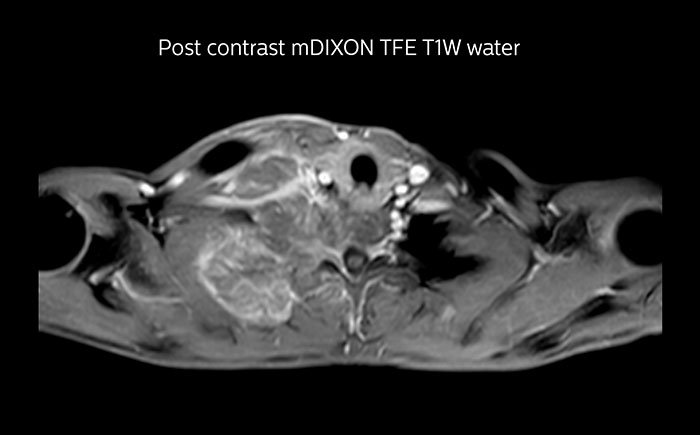

MRI of Pancoast tumor

Although the area between the neck and the top of the lung is one of the most difficult areas for MRI, Prodiva 1.5T images show good quality in this 56-year-old male with Pancoast tumor on the right. mDIXON TFE images shows excellent fat suppression in the neck area and the DWI shows almost no distortion.

MRI of Pancoast tumor

Although the area between the neck and the top of the lung is one of the most difficult areas for MRI, Prodiva 1.5T images show good quality in this 56-year-old male with Pancoast tumor on the right. mDIXON TFE images shows excellent fat suppression in the neck area and the DWI shows almost no distortion.